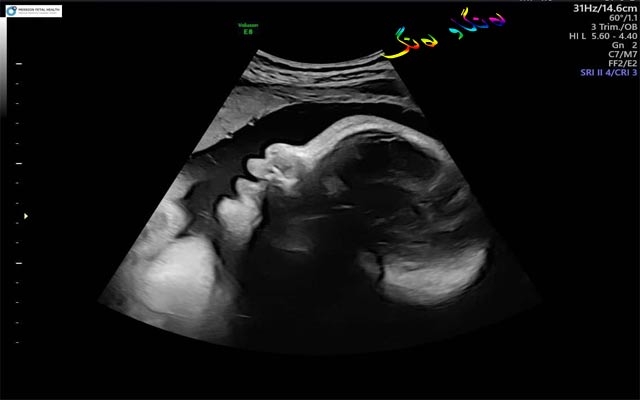

سمێڵی كۆرپەڵە

لە تیشكە پێشكەوتووەكاندا، حاڵەتێكی سەیری كۆرپەلەكان دەردەكەون، كە ئەویش بوونی سمێڵی كۆرپەلەیە، پسپۆڕان دوای پشكنین و شیكردنەوە توانیان ئەو حاڵەتە دیاری بكەن، كە هەموو كۆرپەلەیەك لە ماوەی گەشەكردنیدا لە منداڵداندا لە یەكێك لە قۆناغەكاندا سمێڵێكی بۆ دروست دەبێت، كە دواتر بە هەموو جەستەیدا دابەش دەبێت و پاشان ئەو مووانە دەخوات - مووی بێزیانن. ئەو مووانە بە گەندە موو ناودەبرێن و پاش لە دایكبوونیان لە یەكەم كرداری پیساییكردندا دەریدەدەنە دەرەوە، ئەو پیساییەش ناودەبرێت بە مەكۆنیەم.